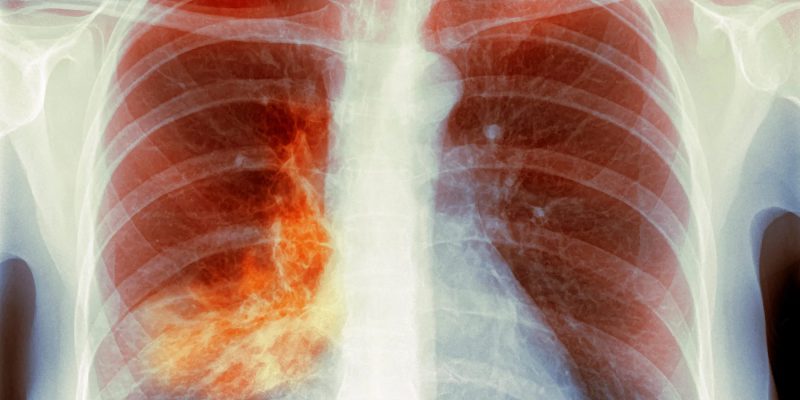

„Weiße Lungen“-Pneumonie – Was Sie wissen müssen

7. Dezember 2023 – Wie besorgt sollten Sie über Ausbrüche der „White-Lung-Syndrom“-Pneumonie bei Kindern sein, die in Ohio, Massachusetts und mehreren Ländern Europas gemeldet werden? WebMD hat Experten diese Frage gestellt und gefragt, ob die Fälle mit einem ähnlichen Ausbruch in China ...